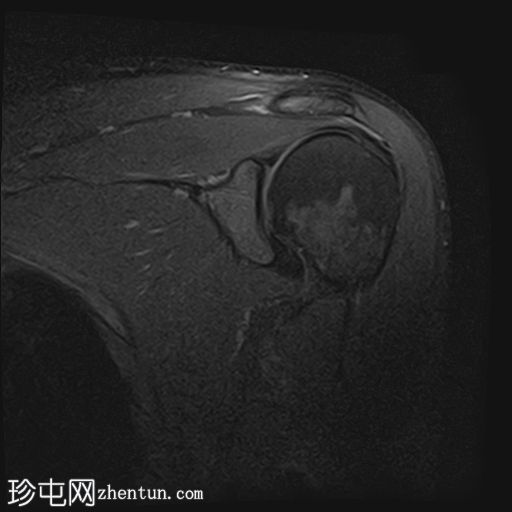

5.jpg

冠状位

T1加权像

冈上肌腱上部纤维可见约25 x 1.2 mm的低信号肌腱内病变,符合钙化性肌腱炎的影像学表现

冈上肌腱滑囊侧纤维可见液体信号增高,符合肌腱病

II型肩峰(弯曲型)

肩峰下滑囊内可见轻度液体信号,提示轻度滑囊炎